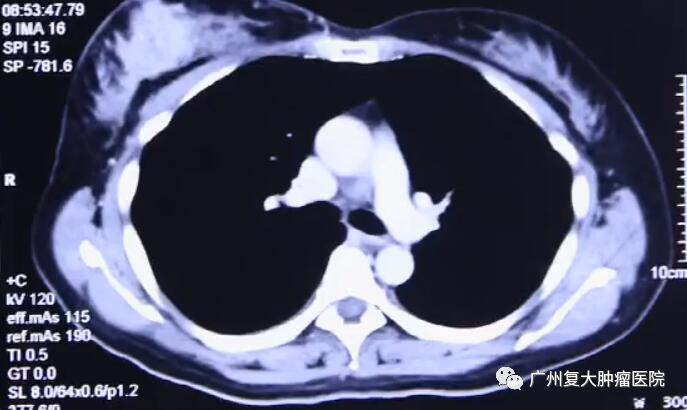

影像結(jié)果顯示

超聲引導下將探針插入腫瘤區(qū)內(nèi),當溫度下降超過一定水平時,冰晶開始在腫瘤細胞內(nèi)部形成,凍結(jié)供應營養(yǎng)的血管,停止運輸養(yǎng)分,摧毀腫瘤細胞組織。持續(xù)幾分鐘后,迅速又復溫。經(jīng)過這樣兩個循環(huán)后,腫瘤病灶完全被“凍結(jié)”,進而達到治療效果。由于病灶位置淺,離皮膚較近,因此在術(shù)中還要對皮膚采取保護措施,以免凍傷皮膚。

3天后Mary就恢復日常活動能力,術(shù)后半年她體內(nèi)的腫瘤指標已下降到正常范圍了。10年來,Mary的健康情況良好,復查顯示腫瘤現(xiàn)在僅剩一個疤痕。